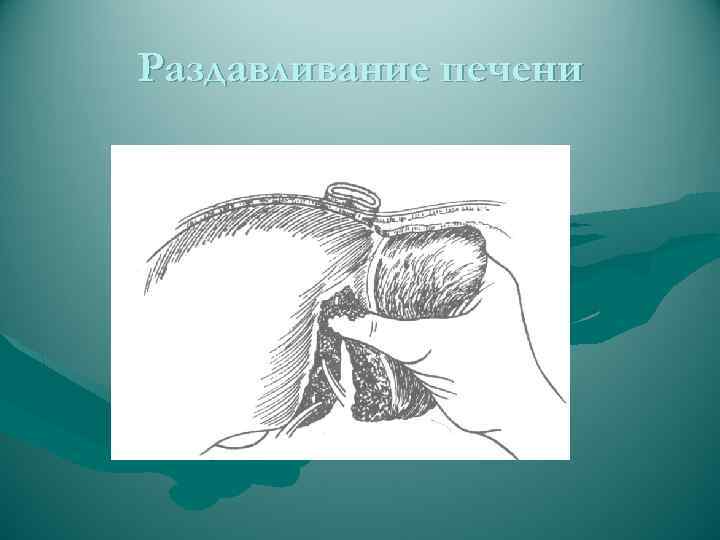

РЕЗЕКЦИЯ ПЕЧЕНИ Атипичные резекции - восточный способ - удаление части органа в пределах здоровых тканей с постепенным, по ходу намеченного пересечения печени, раздавливанием пальцами паренхимы и перевязыванием пальпаторно обнаруженных сосудистых и желчных образований: - краевая - клиновидная - поперечная Основной момент операции - шов печени Преимущество - более экономна с точки зрения количества удаляемой ткани - простота и быстрота Недостаток - возможность опасных неуправляемых кровотечений - возможность некрозов остающихся здоровых участков печени из-за перевязки их сосудов и желчных протоков

РЕЗЕКЦИЯ ПЕЧЕНИ Атипичные резекции - восточный способ - удаление части органа в пределах здоровых тканей с постепенным, по ходу намеченного пересечения печени, раздавливанием пальцами паренхимы и перевязыванием пальпаторно обнаруженных сосудистых и желчных образований: - краевая - клиновидная - поперечная Основной момент операции - шов печени Преимущество - более экономна с точки зрения количества удаляемой ткани - простота и быстрота Недостаток - возможность опасных неуправляемых кровотечений - возможность некрозов остающихся здоровых участков печени из-за перевязки их сосудов и желчных протоков

Раздавливание печени

Раздавливание печени